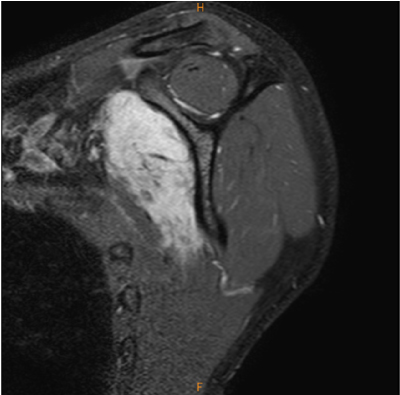

たまたま経静脈性造影が施行されている。

肩甲下筋腫瘍(デスモイド), 棘上・下筋腱関節側部分断裂

![]() |